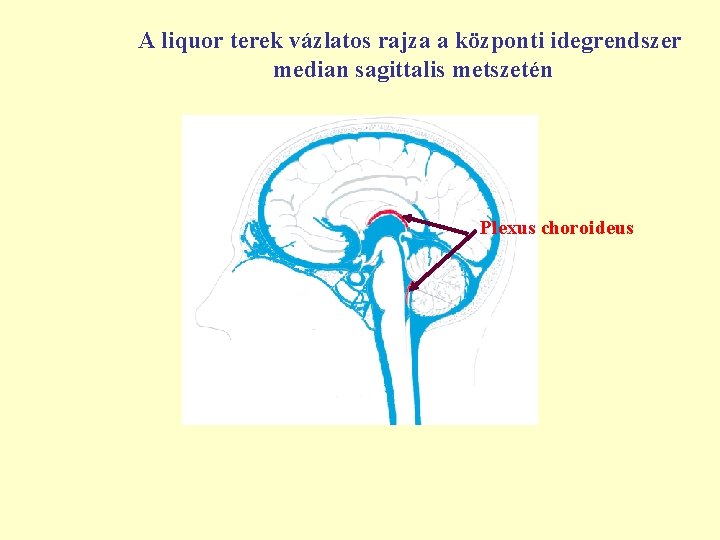

A liquor terek vázlatos rajza a központi idegrendszer median sagittalis metszetén Plexus choroideus